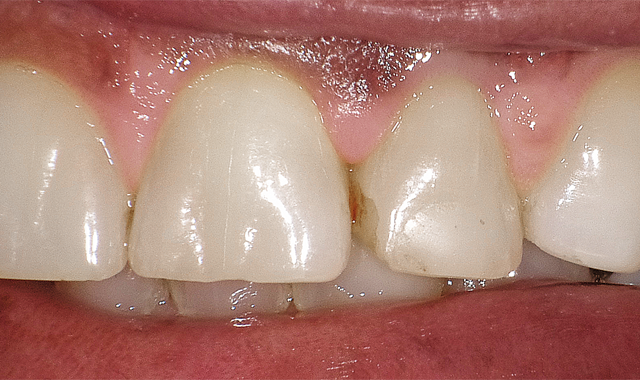

After bevel placement, Palident Matrix System was put in place, followed by selective etching, rinsing, suction drying and application of a universal bonding agent (must be scrubbed for 20 seconds throughout the preparation due to selective etching), appropriate air drying and light curing (Fig. 2).

After bevel placement, Palident Matrix System in place, selective etching followed by rinsing, suction drying and application of a universal bonding agent appropriate air drying and light curing.